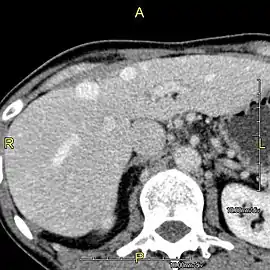

Axial CT image showing anomalous hepatic veins coursing on the liver's subcapsular anterior surface[66]

A CT scan in which the liver and portal vein are shown